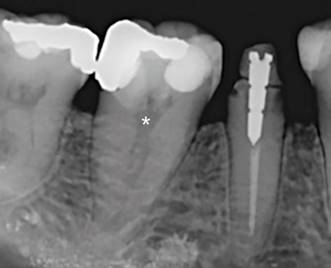

Paciente mujer de 48 años de edad sin antecedentes médicos de mención, fue derivada al Área de Endodoncia de la Clínica Odontológica Docente Asistencial (C.O.D.A.) de la Facultad de Odontología de la Universidad de La Frontera (Temuco, Chile) para realizar tratamiento del primer molar mandibular izquierdo permanente (diente 46), indicado este procedimiento por una posterior rehabilitación protésica. Luego de realizadas las pruebas clínicas usuales, se llegó al diagnóstico de “pulpitis irreversible asintomática con tejidos apicales normales”. El examen radiográfico preoperatorio demostró la presencia de restauraciones profundas, una cámara pulpar levemente retraída y el hallazgo inusual de un canal centrado en una única raíz (Figura 1), de tipo I según la clasificación de Vertucci 13. Informada la paciente de esta situación, consentido el procedimiento, y procediendo al tratamiento endodóntico no quirúrgico de rutina, se realizó el acceso convencional a la cámara pulpar con fresas específicas e instrumental rotatorio. La trepanación permitió la confirmación macroscópica de un único gran canal localizado en el centro de la cámara pulpar, el cual fue preparado quimiomecánicamente siguiendo los protocolos estándar de la institución. Debido a la "particularidad" de la anatomía canalicular, y para evaluar potenciales presencias de canales accesorios o enmascaramientos morfológicos que pudieran condicionar el éxito del procedimiento, se consideró realizar CBCT antes de continuar con el tratamiento endodóntico en una sesión posterior.

Figura 1: Radiografía periapical. Nótese la imagen difusa de un canal centrado en una única raíz en el primer molar mandibular (*), hallazgo sumamente infrecuente